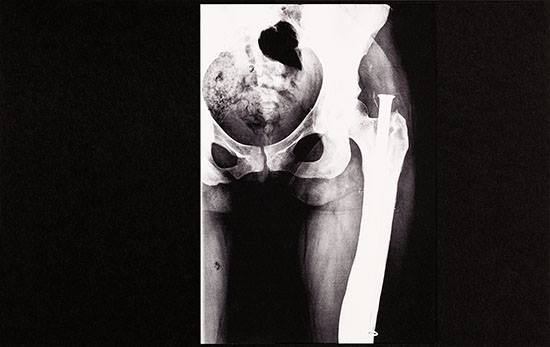

O que acontece quando se juntam cinco fotógrafos e professores de fotografia com vontade de criar algo completamente diferente no panorama das publicações do género em Portugal? Uma revista que é muito mais do que uma revista. O número zero da propeller foi apresentado no passado dia 22 de Junho em Lisboa e é diferente. O papel é diferente, a capa é diferente e toda a apresentação exterior joga com o interior de modo a criar uma identidade muito própria. Não se pode esperar um objecto que se folheia facilmente. Não é. A propeller chegou para agitar consciências e ideias e escolheu como primeiro tema a pornografia. A escolha não poderia passar por um caminho fácil. A propeller é um projecto da HÉLICE, escola de fotografia composta por Duarte Amaral Netto, João Paulo Serafim, Rodrigo Tavarela Peixoto e Valter Ventura. Os quatro compõem o Conselho Editoral da publicação, que foi entregue a Sofia Silva para coordenar. Mistura-se fotografia de autor com conteúdo académico, um dos objectivos da publicação. Para Sofia Silva, “o objectivo primeiro é fazer uma revista de fotografia de autor, promover trabalhos novos e arriscar, pensar temas diferentes e assumir este risco de publicar trabalho novo”. Neste número zero, os trabalhos de Sasha Kurmaz, Pedro Medeiros, Tânia Simões, Paula Rae Gibson, João Pedro Vale e Nuno Alexandre Ferreira, Bruna Prazeres, André Cepeda, Mané e António Júlio Duarte cruzam-se com os textos de Marta Sicurella, Vítor Belanciano e Manuel José Damásio. Pelo meio, uma conversa com Alfredo Jaar e uma mesa redonda sobre pornografia, estética, ética e feminismos. Que não se pense que o tema da pornografia seja tratado de forma evidente, como um assunto fechado sobre si. Os autores foram desafiados em função do seu corpo de trabalho ter algo a ver com o tema e há aqui trabalho novo e trabalho de gaveta. Assume-se um carácter experimental e um risco - “se vais buscar um trabalho já feito e arrumas as coisas todas estruturadas tende a não haver risco”, explica a coordenadora. Por opção editorial, não há sinopses dos trabalhos. No entender de Sofia Silva, vivemos um nicho onde tudo tende “a ser muito mais sobre o valor nominal da obra, de quem é, do que sobre o trabalho”. Aqui não se explicam trabalhos, deixa-se espaço para que ao pegar na propeller cada um seja invadido por aquilo que cada imagem ou texto lhe transmitir. Contra a ideia de arte como algo que serve fins determinados e pela arte como criação de uma nova linguagem e articulação do novo. Contra textos explicativos que condicionam o olhar de quem vê, pela experiência de olhar a obra como uma “mancha que provoca uma experiência estética”. Daí a opção também por um tema que não seja trabalhado de forma fechada sobre si. O objectivo é deixar que toda a forma “seja qualquer coisa que se aproxime do pornográfico”, afirma a coordenadora. O tema é tratado de forma política. A pornografia levanta inúmeras questões acerca do seu limite moral e algumas delas são tratadas na mesa redonda sobre pornografia, estética, arte e feminismos. Não é estranho que esta conversa surja logo a seguir ao trabalho de Paula Rae Gibson, a obra que na propeller mais incide sobre a sexualidade feminina. E esta parece ser uma das facetas mais demarcadas deste número zero. Entre obras como a de Sasha Kurmaz, com uma forte objectificação feminina, e a de Bruna Prazeres, com a imagem mais forte de toda a publicação - de uma vagina cosida - trata-se do tema da pornografia de uma forma heterogénea, com uma multiplicidade de visões e mensagens, mas sem nunca deixar passar em claro o problema político da forma como as mulheres são tratadas nas imagens que assumimos como pornográficas. Na conversa com Alfredo Jaar, o artista chileno define a pornografia como a exploração sexual de qualquer corpo humano com propósitos puramente comerciais. No seu entender, a imagem pornográfica provoca um dano filosófico na sociedade ao criar um modelo da forma como se devem tratar as mulheres. Mas nem só de uma visão da mulher na pornografia vive a propeller. A publicação abre com Man Ray, com uma das imagens de “As Quatro Estações”. Foi a partir de “Été”, lê-se no editorial, que se começou a desenhar este número zero. Entende-se porquê, já que nos questionamos porque é que aquela imagem não fere tantas susceptibilidades como poderá ferir uma imagem dita pornográfica. Se a imagem explícita de uma penetração está presente, porque não o choque? A propeller vai mais longe e lança a discussão para os limites da representação fotográfica: porque é que uma cena de sexo explícito tende a ficar aquém daquilo que se define como uma obra de arte? Existe algo na representação sexual que seja impossível de ser esteticizado? O trabalho do fotógrafo Pedro Medeiros, “Sex Pixel”, apresenta imagens pixelizadas de expressões de prazer, submissão e dor. Descaracteriza-se o cenário do filme pornográfico e centra-se a acção nas sensações transmitidas pelos intervenientes. Apesar do carácter directo das sensações, acaba por haver um certo distanciamento pelo destruir da realidade que está à volta, um duplo distanciamento conseguido pela pixelização das imagens. Um distanciamento do pornográfico e do real. O que fica então quando se olha a esta distância e com esta proximidade? Ao olhar as imagens de Mané, podemos dizer que a pornografia está nos olhos de quem a vê. Uma assimilação entre as árvores e os corpos humanos. Uma sexualização da natureza ou a naturalidade do sexo? Afinal o que é que nos choca? A imagem? A sugestão? Num trabalho mais estético do que pornográfico, e que o será porque nos deixa muito espaço para ir para além da obra, há imagens muito gráficas, que enquanto retratos de corpos humanos seriam pornográficas mas que sendo de árvores se tornam puramente estéticas. Podemos dizer que é a introdução do corpo humano que traz a ideia do pornográfico? E será só isso? A publicação termina com RXPorn, trabalho de António Júlio Duarte. São imagens de partes de corpos, em radiografias, todos eles com próteses. Uma relação entre o corpo humano e o mecânico que, se nos lembrarmos da utilização de próteses em alguma pornografia, levanta mais uma vez a questão do limite da imagem pornográfica. Este trabalho, juntamente com o de Mané, leva longe a questão da pornografia. A propeller oferece uma multiplicidade de abordagens, fotográficas e teóricas, num número limitado de 150 exemplares que merece ser comprado e visto. Faltarão algumas visões mais subversivas como a de Beatriz Preciado, que afirma a existência de uma tecnologia sexual que identifica os órgãos reprodutores como órgãos sexuais, em detrimento de uma sexualidade de todo o corpo. Faltará também Judith Butler, quando diz que é um falso pressuposto assumir que todo o sexo hetero é fálico e todo o sexo fálico é hetero. Mas isto não belisca em nada o carácter enriquecedor da publicação no actual panorama nacional. É um produto bom, novo, que traz o novo. Os objectivos foram cumpridos, no entender de Sofia Silva: “é uma abordagem honesta, pouco controlada, não gosto que as coisas estejam muito controladas, limadas e polidas, parece que estão muito fechadas e muito finalizadas. Há um certo desarrumo que é bom. É bom que tenha dado início a conversas e vá dar início a mais conversas”. Com periodicidade bimestral, a próxima edição será lançada a 22 de Dezembro. O tema já é conhecido: a mancha. E há um Open Call aberto a participações. Podemos esperar de novo algo totalmente diferente. A edição é feita pela Stolen Books e os formatos físicos das publicações não são para ser repetidos. Cada número assumirá o formato que o tema pedir, numa lógica mais de livro de artista do que uma revista pura e dura. De salientar o carácter manual da edição de lançamento, onde as fotografias foram impressas em jacto de tinta a laser, montadas em cartolinas e depois fotografadas. Esta mistura de trabalho manual com imagem digital é mais um carácter distinto da propeller: a tentativa de que a publicação, como objecto, ajude a tratar o tema ou esteja de acordo com o que foi a montagem. A propeller veio rasgar conceitos fechados, agitar consciências e abrir discussões. Já se disse que é um projecto diferente?